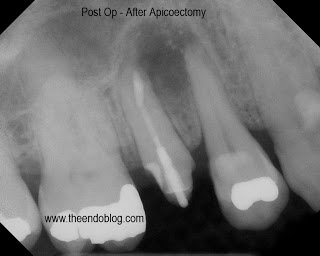

9 month recall show complete healing of the periapical lesion, tooth is fully functional and asymptomatic. This procedure saves the patient significant time and money over extraction and implant placement.